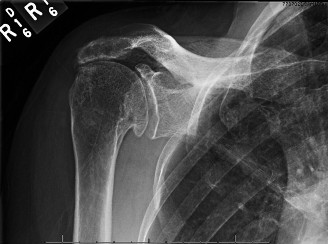

Treat a patient with infected total shoulder arthroplasty? CASE 21 A 70-year-old, right-hand-dominant female presents to clinic complaining of 4 years of gradually worsening chronic right shoulder pain and stiffness. She says the pain is worse at night and with any range of motion, denies a history of trauma, pain in other extremities, or numbness or tingling of the right upper extremity. She notes that her mother suffered from rheumatoid arthritis that affected her shoulder. Physical examination reveals decreased muscle bulk over the right supra- and infraspinatus fossae compared to the contralateral side, limited active and passive ROM, marked weakness with external rotation, and 4+/5 strength with shoulder abduction. X-rays of the right shoulder are shown in Figures 2–58 and 2–59.

Figure 2–58

Figure 2–59

The correct answer is (C). Rotator cuff tear arthropathy consists of a combination of rotator cuff insufficiency, glenohumeral joint degenerative changes, and superior humeral head migration. It is more common in women and also more often found on the dominant side. The patient’s clinical examination with weakened external

rotation and muscle atrophy signaling incompetent supra- and infraspinatus muscles point to rotator cuff insufficiency, and her plain films reveal narrowed glenohumeral joint space as well as superior migration of the humeral head. Choice D is incorrect because, while radiographs would show narrowing of the glenohumeral joint space, they would also likely show numerous osteophytes and posterior wear of the glenoid. Choice B is incorrect because, while adhesive capsulitis does present as decreased active and passive range of motion, the patient’s constellation of symptoms pointing towards rotator cuff insufficiency along with the radiographs make cuff tear arthropathy the more likely choice. Finally, Choice A is incorrect because even though she has a positive family history of rheumatoid arthritis, it is less likely to present only in a single joint. Also, rheumatoid arthritis on radiography appears more as an erosive process without the characteristic superior migration of the humeral head.

The correct answer is (A). Superior migration of the humeral head would be most indicative of chronic rotator cuff insufficiency associated with cuff tear arthropathy, as it is a direct result of the inability of the rotator cuff tendons to help maintain the humerus in its normal position. Acetabularization of the undersurface of the acromion is commonly associated with superior migration of the humeral head found in rotator cuff tear arthropathy, and can be assessed using the Hamada classification, which is based on measurements of the acromiohumeral interval on radiography (Table 2–8). Choices B and C are incorrect because, while narrowed glenohumeral joint space and subchondral sclerosis are associated with rotator cuff arthropathy on radiographs, they indicate degenerative joint changes rather than chronic rotator cuff insufficiency. Choice D is incorrect because it is not a specific sign of rotator cuff arthropathy.